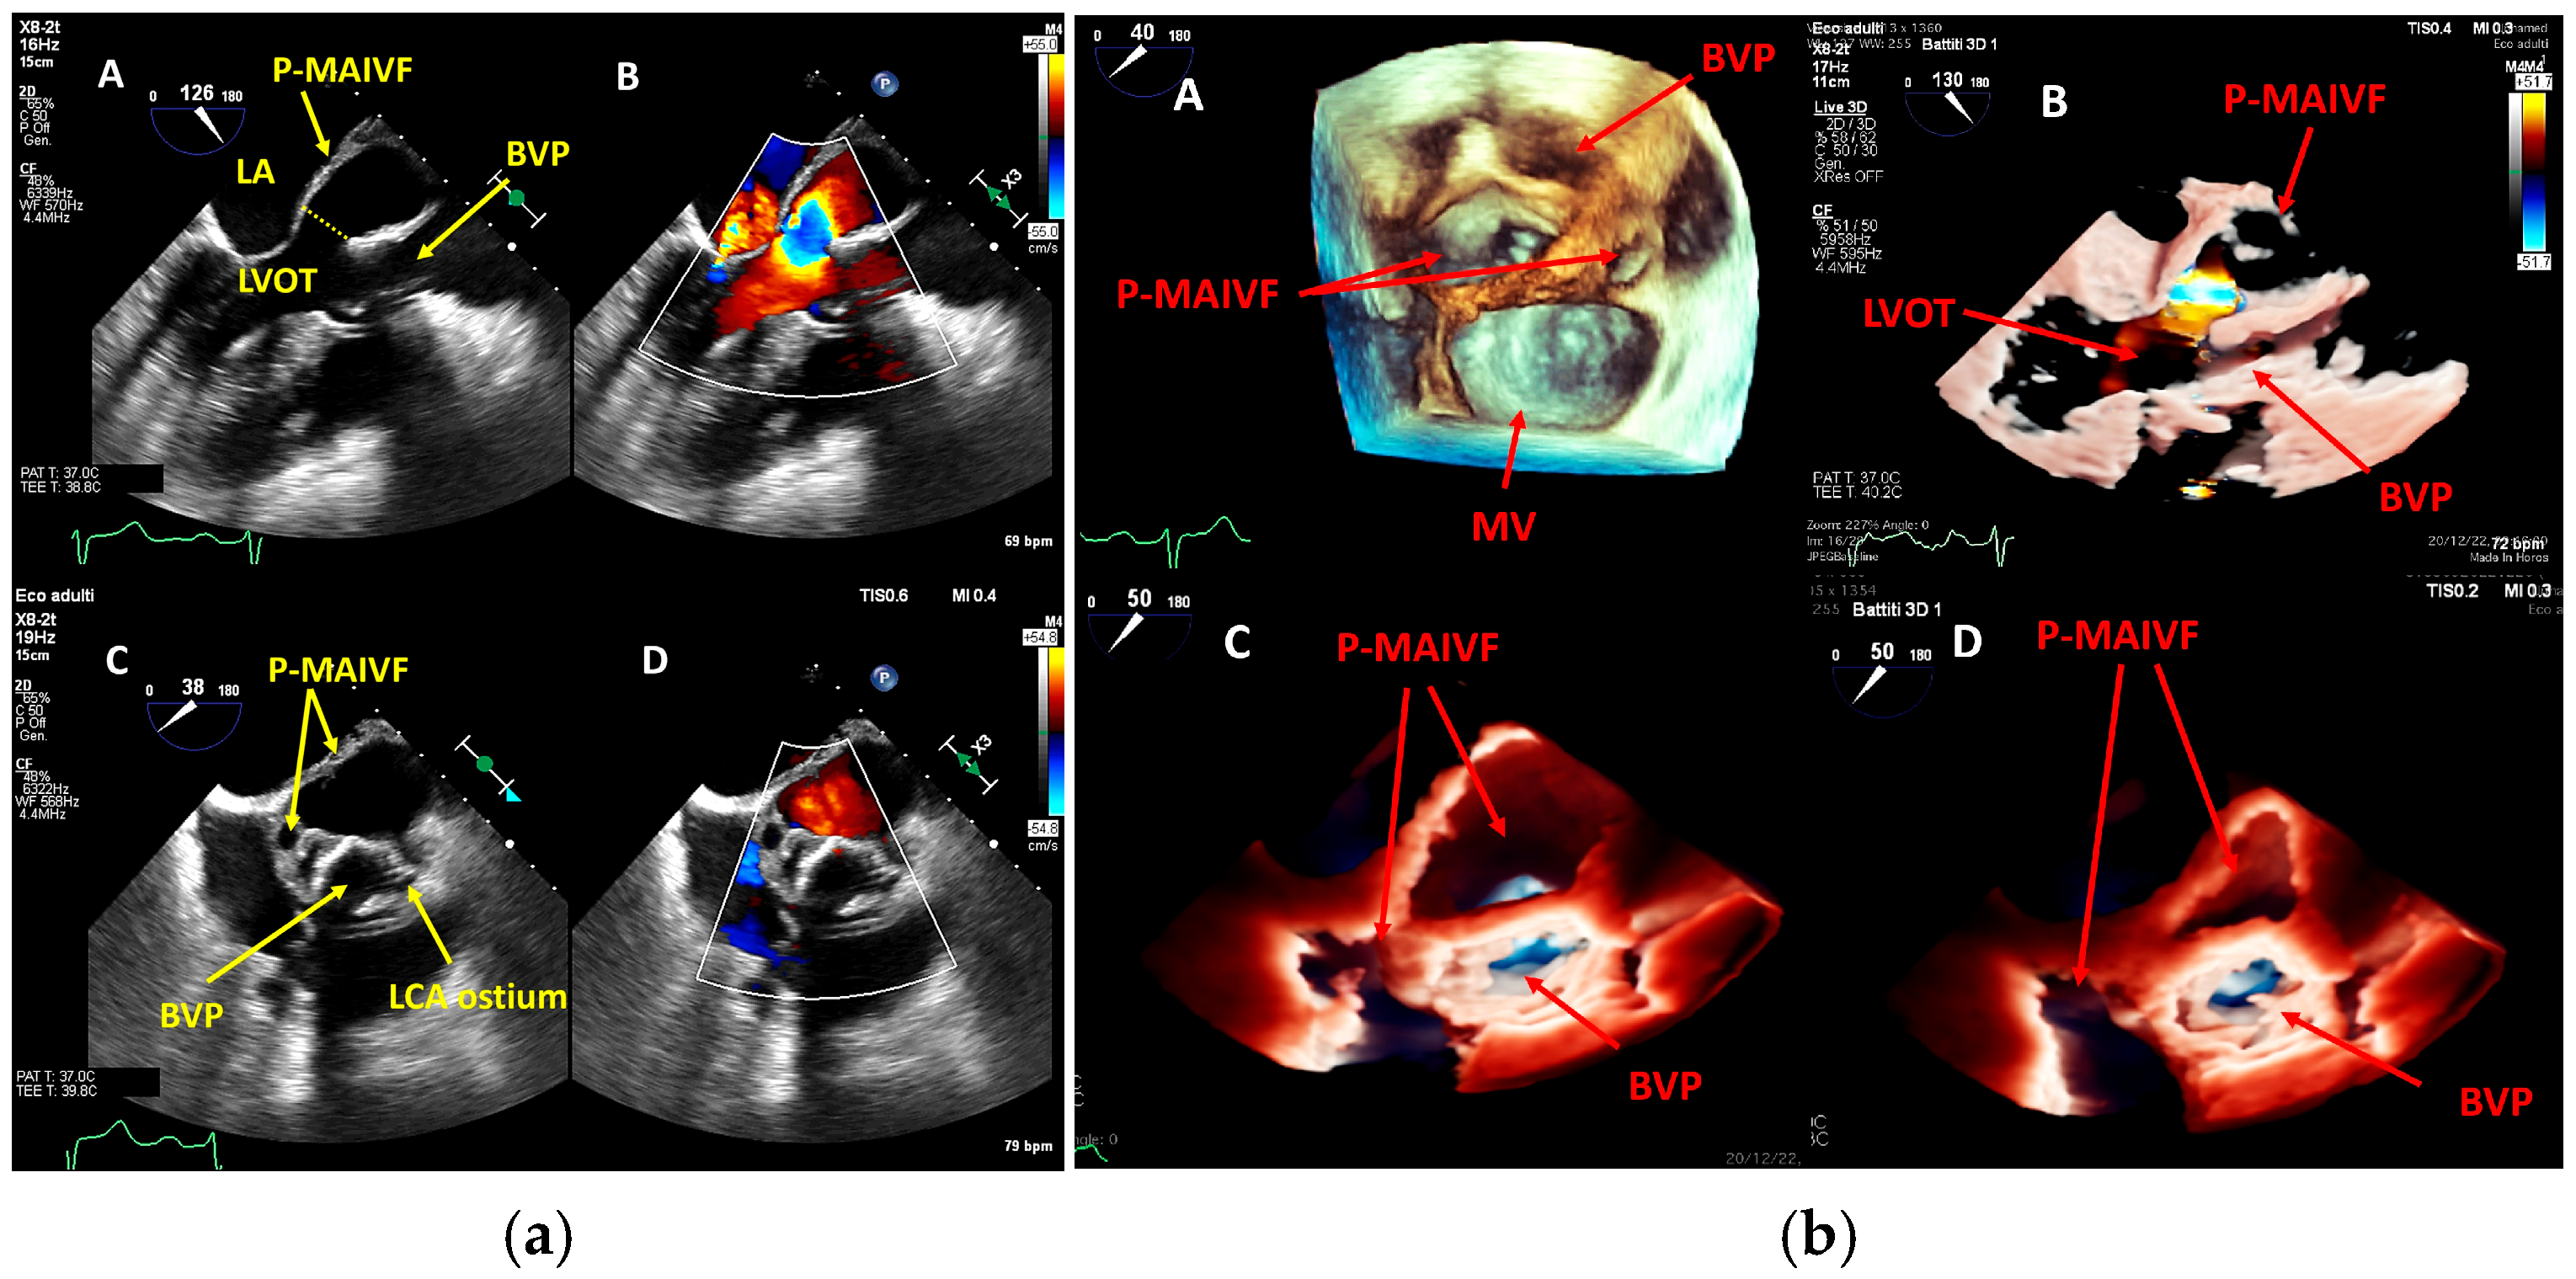

4. Echocardiography

- perivalvular or perigraft abscess, an echolucent or echodense area adjacent to the valve annulus or prosthetic ring often with irregular borders and sometimes with evidence of cavity formation.

- pseudoaneurysm, a contrast-filled outpouching with a narrow neck communicating with the cardiac lumen, often adjacent to the valve annulus. On echocardiography, it appears as a pulsatile cavity with systolic expansion and diastolic collapse.

- intracardiac fistula, visualized as an abnormal communication between cardiac chambers or vessels, is often detected by using color Doppler.

- significant new valvular regurgitation compared with previous imaging, i.e., increase in regurgitant jet size, vena contracta width…